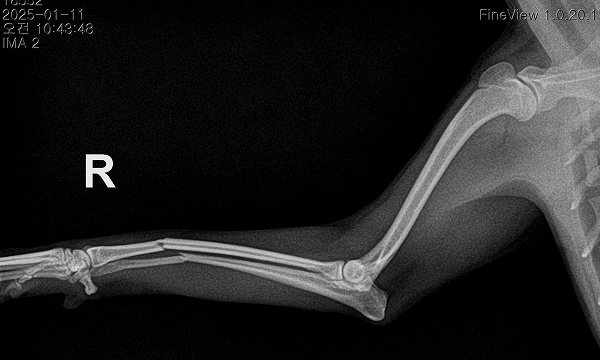

수술케이스 ② 보*강아지 - 요척골 단순골절

수술케이스 2 before BEFORE

수술케이스 2 after AFTER